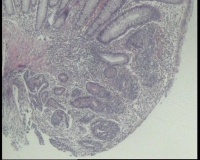

横结肠中部见一增生性肿物大小2.0x1.5厘米,表面糜烂充血,取材2块

2块组织内有1块正常,另一块局灶腺体异型,细胞复层排列,细胞核异型不太大,局灶够高级别吗?